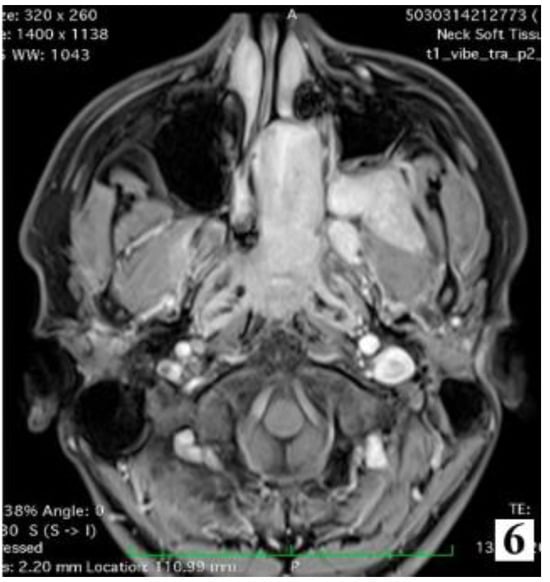

Figure 6.

IIA—Minimal lateral extension into the pterygopalatine fossa; IIB—Full occupation of pterygopalatine fossa with or without superior erosion orbital bones (part 2).

For stages IIA-IIB, the trans-nasal surgery is indicated, following the same steps as for stages IA and IB.

Magnetic resonance imaging provides important details about the extension of the tumour. T2 weighted sequences are indicated to differentiate tumour tissue from mucus, while T1 weighted sequences are indicated for better assessment of intracranial extension [5].